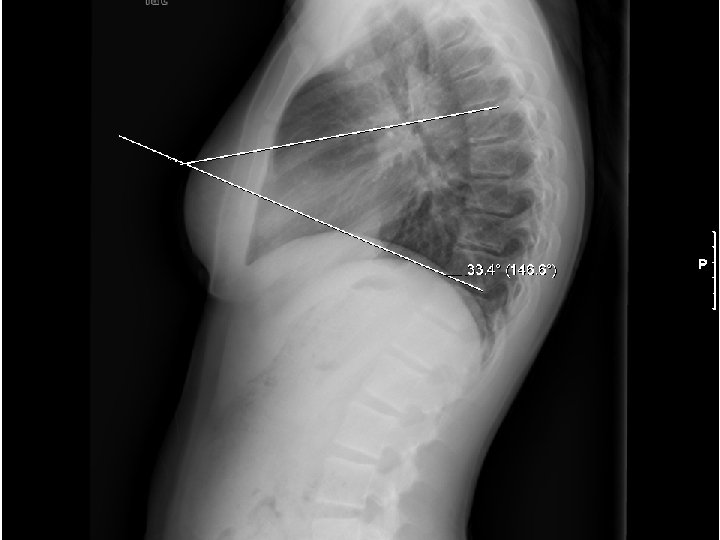

Measure spinal curvature using Cobb method: - Choose the most tilted verterbrae above & below apex of the curve. - Angle b/t intersecting lines drawn perpendicular to the top of the superior vertebrae and bottom of the inferior vertebrae is the Cobb angle.

Measure spinal curvature using Cobb method: